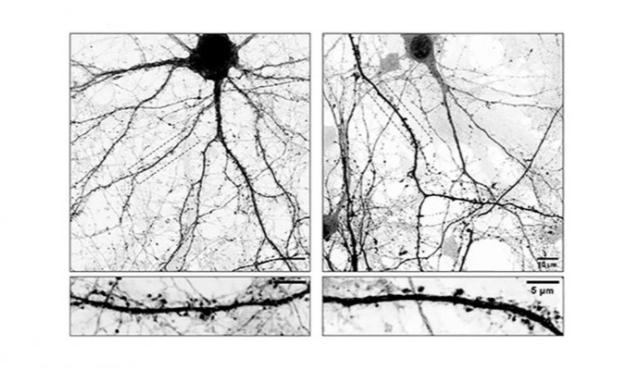

16/01/2026 Investigadores del CONICET lograron identificar mecanismos celulares y moleculares clave involucrados en la progresión de la enfermedad de Parkinson, un avance que podría abrir un nuevo camino para optimizar las terapias actuales,...

05/02/2026 Un equipo de científicos del CONICET desarrolló un software basado en Inteligencia Artificial que permite analizar proteínas asociadas a enfermedades neurodegenerativas como el Alzheimer y el Parkinson, entre otras patologías que...